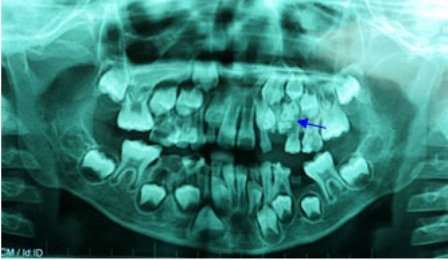

| Hình ảnh X-Quang cho thấy túi răng nằm trong miệng bệnh nhi |

Bệnh nhi được tiến hành chụp phim X-quang để khảo sát, bác sĩ phát hiện có một khối cản quang ở vùng xương hàm trên bên trái, nằm cạnh khối u là chiếc răng nanh sữa. Qua kết quả trên, bác sĩ chẩn đoán bệnh nhân bị u răng, khối u nằm choán hết đường di chuyển của răng nanh sữa và chắn ngang đường mọc lên của hai răng vĩnh viễn số 3 và số 4.

Bác sĩ đã tiến hành phẫu thuật cắt bỏ khối u xương hàm trên có kích thước 3x3x2cm cho bé. Khối u này gồm nhiều tiểu thể nhỏ kết dính lại với nhau, được bao bọc bằng một bao xơ dày dai chắc. Chia tách u để khảo sát, bác sĩ ghi nhận có tới 54 chiếc răng nhỏ bên trong.